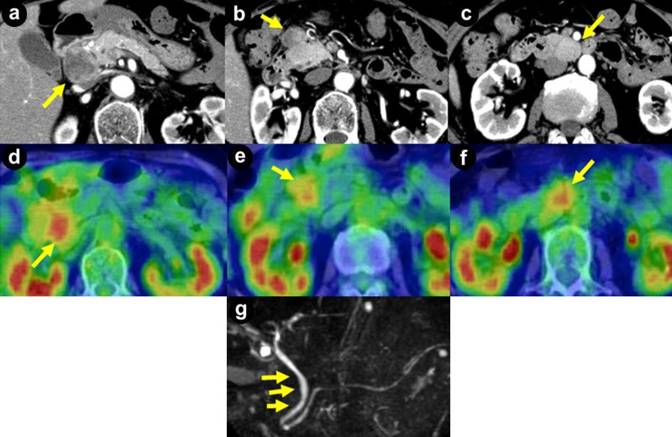

A 72-year-old woman was admitted to our hospital in 2012 after detection of a pancreatic head mass during follow-up ultrasonography for an ovarian cystic tumor. She was asymptomatic. Abdominal examination revealed no tenderness or palpable mass. She had a past history of cerebral infarction, but no other comorbidities including diabetes mellitus. She had no family history of malignancy. Laboratory test results including blood cell counts, blood biochemistry, tumor marker levels (carcinogenic embryonic antigen and carbohydrate antigen 19-9), and serum hormone levels (gastrin, insulin, calcitonin, prolactin, and intact parathyroid hormone) were all within normal limits. Enhanced computed tomography showed a low-density mass measuring 37 mm in diameter in the head of the pancreas (Figure 1a) and enlarged lymph nodes on the anterior surface of the pancreatic head (Figure 1b) and the posterior surface of the horizontal part of the duodenum (Figure 1c), measuring 28 mm and 34 mm in diameter, respectively. No liver metastasis was identified. 18F-fluorodeoxy-glucose positron emission tomography showed increased uptake in all three lesions with a maximum standardized uptake value ranging 3-4 (Figure 1def). Magnetic resonance cholangiopancreatography showed that the middle portion of the common bile duct was shifted to the left by the tumor in the head of the pancreas (Figure 1g). There was no dilation of the bile duct or the main pancreatic duct. EUS showed a hypoechoic mass measuring 37×30 mm in the head of the pancreas (Figure 2a) and two hypoechoic masses measuring 25×15 mm each adjacent to the pancreatic head (Figure 2bc). Selective angiography showed two hypervascular tumors in the head of the pancreas supplied by the gastroduodenal artery (Figure 2d), and a third tumor supplied by the inferior pancreaticoduodenal artery (Figure 2e). Histological examination of a biopsy specimen of the pancreatic head mass obtained by EUS-FNA using a 22-gauge needle showed a proliferation of uniform polygonal cells with hyperchromatic round nuclei and eosinophilic fine granular cytoplasm arranged in alveolar nests, sheets, or partial rosette-like patterns (Figure 3a). There were few mitotic figures. Immunohistochemical staining showed that many of the tumor cells were positive for somatostatin (Figure 3b), synaptophysin (Figure 3c), and chromogranin A (Figure 3d), but negative for glucagon, CD38, CD56, and pancreatic polypeptide. The MIB-1 labeling index was less than 5% (Figure 3e). Considered together, these findings led to a tentative preoperative diagnosis of somatostatinoma of the pancreas with lymph node metastases.

Figure 1. Enhanced computed tomography showed a low-density mass measuring 37 mm in diameter in the head of the pancreas (a.) and enlarged lymph nodes on the anterior surface of the pancreatic head (b.) and the posterior surface of the horizontal part of the duodenum (c.), measuring 28 mm and 34 mm in diameter, respectively. 18F-fluorodeoxy-glucose positron emission tomography showed increased uptake in all three lesions, with a maximum standardized uptake value ranging 3–4 (d. e. and f.). Magnetic resonance cholangiopancreatography showed that the middle portion of the common bile duct was shifted to the left by the tumor in the head of the pancreas (g.). |